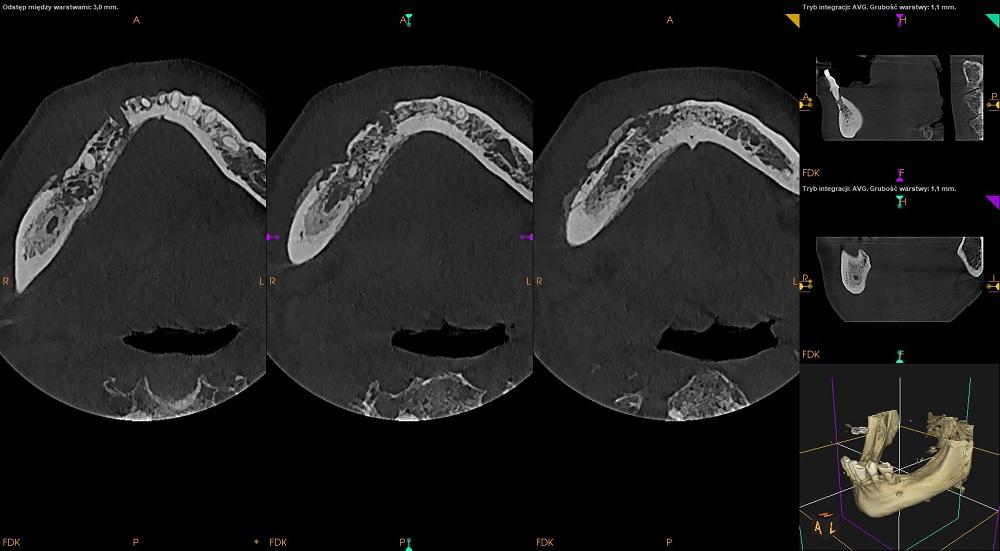

CBCT żuchwy

Badanie CBCT ukazuje chorobowo zmieniony obszar kości trzonu żuchwy po stronie prawej.

W obrazie kości można stwierdzić zatarcie prawidłowego obrazu beleczek kości gąbczastej.

Nieostro ograniczone ogniska osteolizy - obraz kości jak gdyby "wyjedzonej przez mole", a pomiędzy nimi obszary prawidłowej kości.

Występują odczyny okostnowe - festonowate nawarstwienia nowej kości.

W obszarze chorobowo zmienionym - okolica 45 widoczny pozostawiony korzeń zęba oraz fragment tkanki korzenia w okolicy 46/47.

Widoczny zarys zębodołu w okolicy 43.

Obraz radiologiczny odpowiada przewlekłemu zapaleniu kości - osteomyelitis.